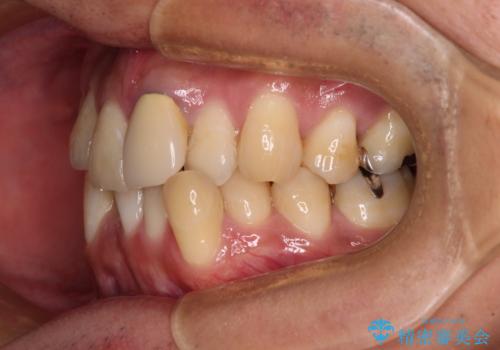

- 下顎の八重歯を気にして来院された患者様です。

左下以外、3本の第一小臼歯が既に抜去されており、左下は八重歯になっている状態でした。

左下の八重歯は手前に傾斜していたため、インビザラインによる抜歯矯正が可能と判断し、後方にある第一小臼歯を抜歯してインビザラインにて矯正治療を行うこととしました。

ワイヤー矯正と比較すると、八重歯が後方に傾斜した仕上がりとなりましたが、患者様ご希望のインビザラインにて十分な歯列を達成することができました。